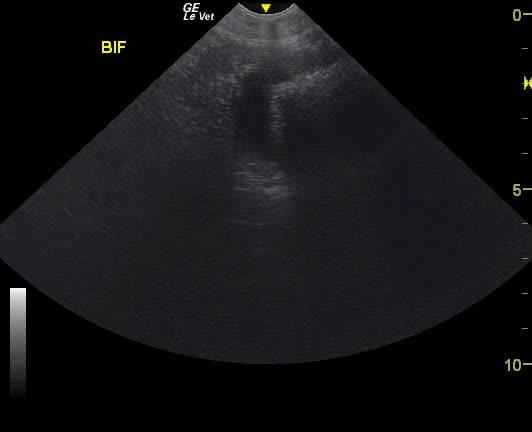

A NM Labrador with a history of foreign body ingestion was presented for intermittent diarrhea that had initially responded to bland diet, metronidazole and aminopentamide. More recently there had vomiting and he appeared uncomfortable. On physical examination, a palpable mass in the cranial abdomen was present. CBC was within normal limits and serum biochemistry showed elevated phosphate low BUN.